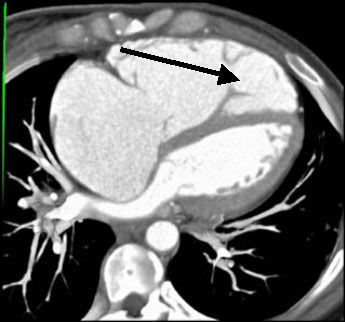

4. Идентификации тромба в ушке левого предсердия. У пациентов с пароксизмальными формами фибрилляции предсердий, для решения о дальнейшей тактике лечения необходимо уточнить наличие тромба в ушке левого предсердия. Обычный способ диагностики - чрезпищеводная ЭХОКГ. Альтернатива чрезпищеводной ЭХОКГ - это проведение более комфортной МСКТ.

![]() |

| Рис.26. Добавочная правая легочная вена (стрелка) выявленная при МСКТ(A) и трансторакальной ЭХОКГ(B). Общее устье (двойная стрелка) левой легочной вены выявленное при МСКТ (C) и трансторакальной ЭХОКГ (D). |

| Рис.28. МСКТ сердца, миксома левого предсердия (стрелка) |